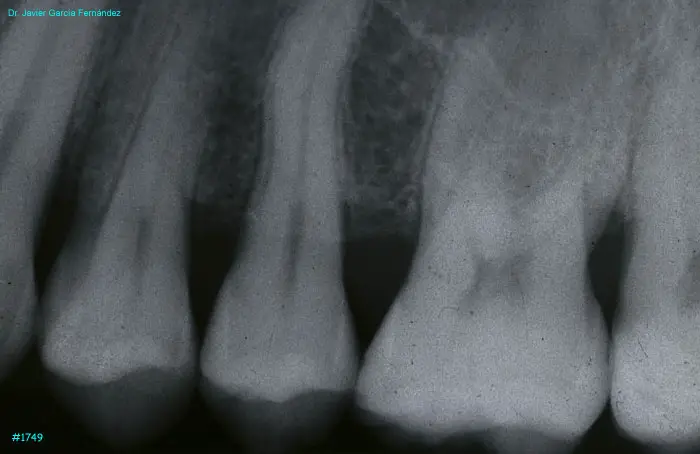

image 17